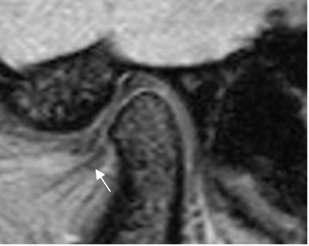

No confundir el disco desplazado, con la inserción del músculo pterigoideo lateral en el cóndilo mandibular, por debajo de la ubicación del menisco. (2). (Fig 12).

Fig 12. Músculo Pterigoideo normal.

RM sagital oblicua en GE. Músculo normal, por debajo de la banda anterior del disco.